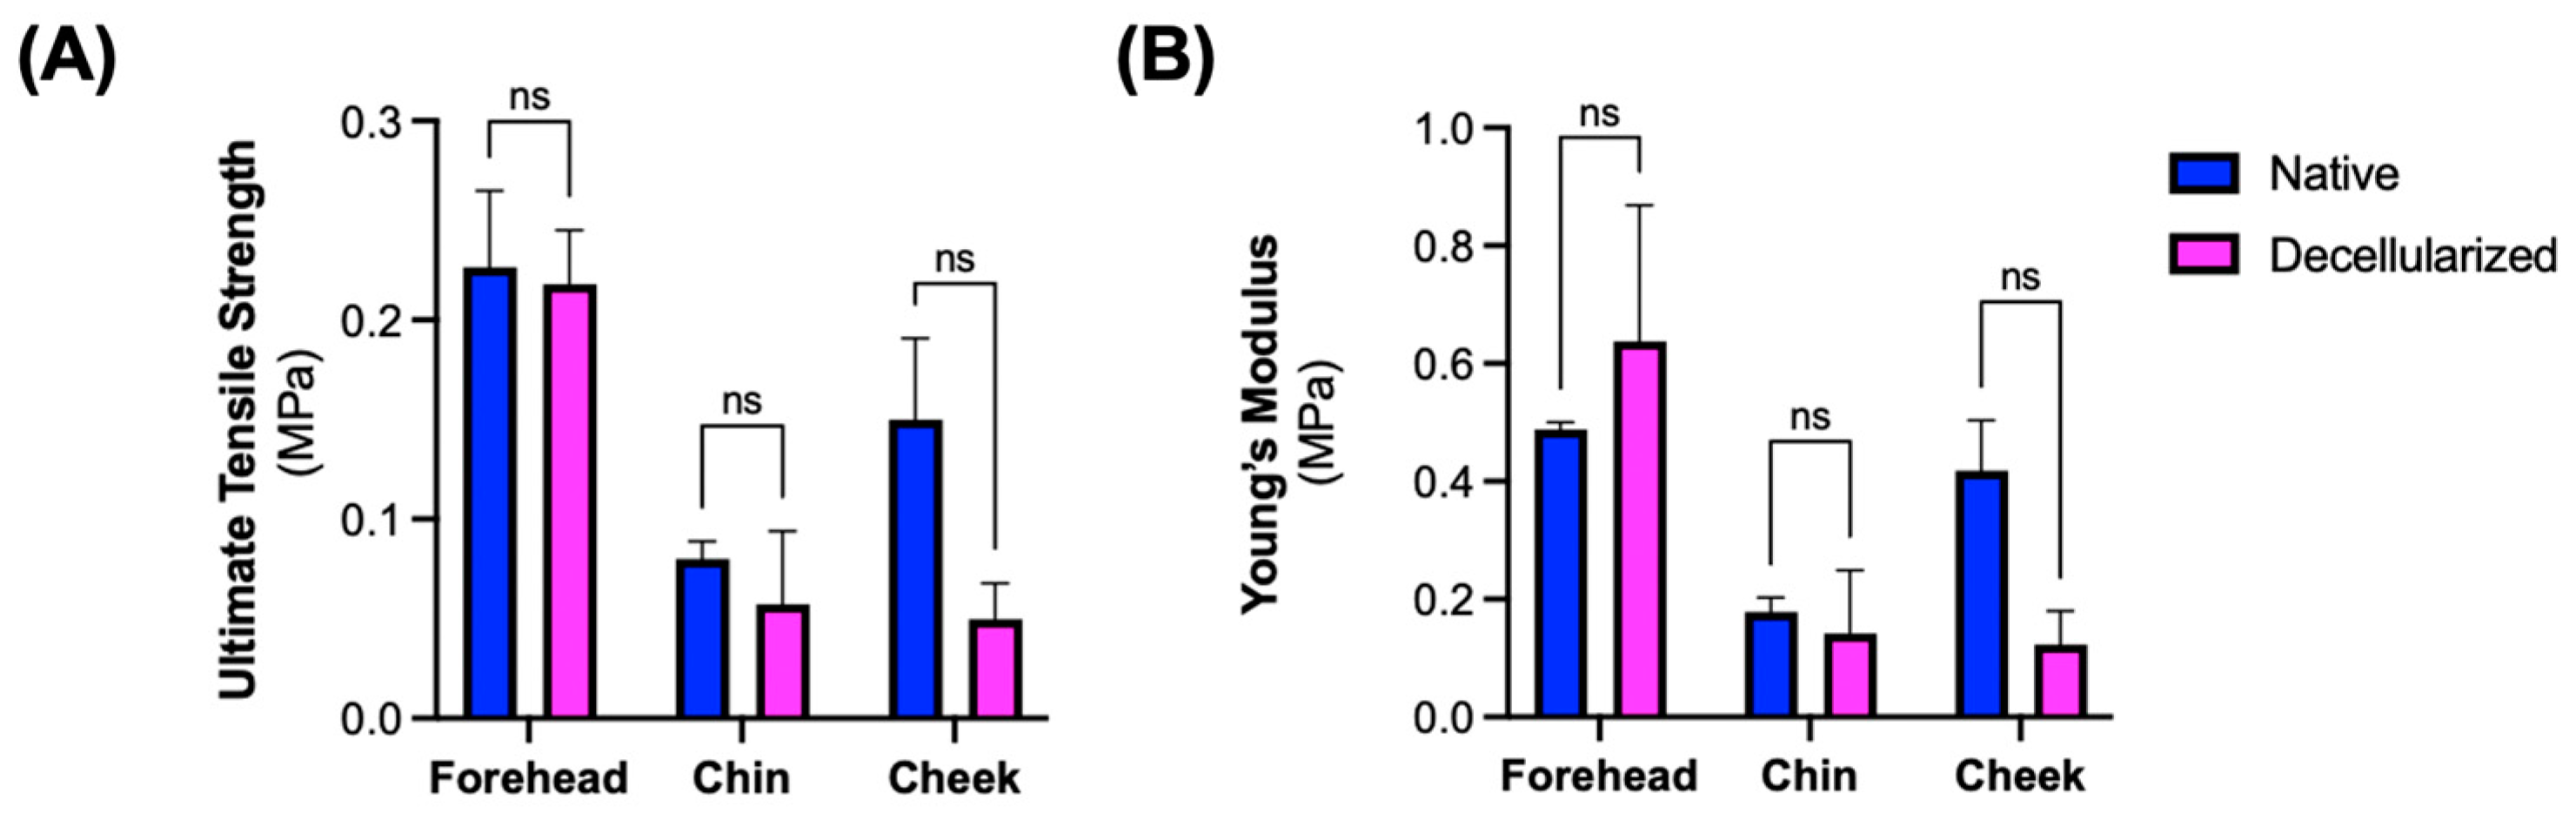

3.3. Microarchitectural and Mechanical Characteristics of Decellularized Facial Grafts